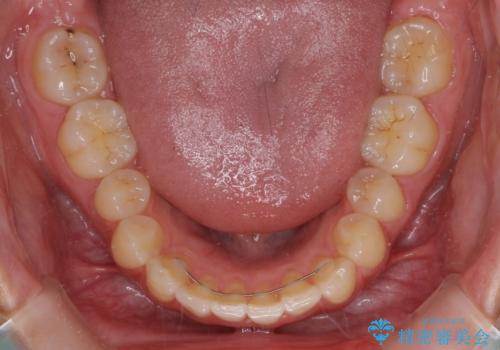

インプラントによる補綴治療とインビザライン矯正

- 抜歯が必要と診断された奥歯を気にして来院された患者様です。

抜歯の上インプラントによる補綴治療を行うこととなりましたが、前歯の叢生も気になるとのことで並行して矯正治療を行うこととしました。

歯列不正は軽微であったので、インビザラインによる矯正治療とし、矯正治療中にインプラント埋入を行う予定としました。

痛みがないので、ボロボロのまま放置していましたが、抜歯後は汚れが溜まりにくくなりスッキリとしたようです。

前歯のデコボコも解消され、ブラッシングが楽になりました。